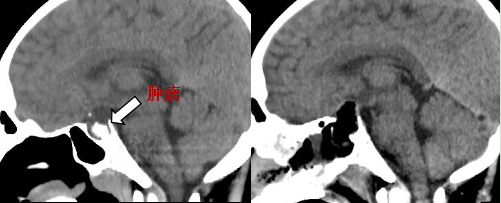

手术中,团队凭借精湛的技术,借助高清神经内镜,犹如赋予外科医生一双“会拐弯的透视眼”。他们通过患者自然腔道——鼻腔,建立微小的通道,精准抵达颅底深处的鞍区。在内镜放大数十倍的清晰视野下,肿瘤与周围正常垂体、颈内动脉、视神经的关系一目了然。逐步剥离肿瘤与周围组织的粘连,历时4小时顺利完成全切除,术中出血量不足30毫升。术后患者意识清醒,视力正常无下降,无脑脊液鼻漏。

术前术后CT影像